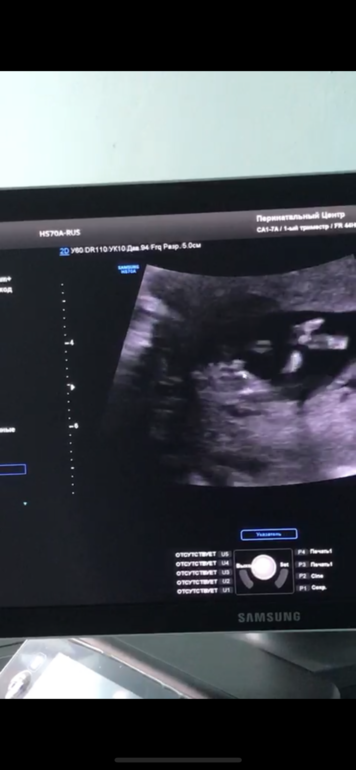

Узи 12 недель, написали приблизительно девочка, а Вы что скажите?

Вопросы про УЗИ, обследования и анализы: что, где, как, когда?